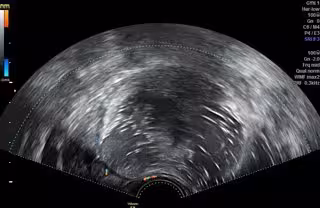

Ecografía Transvaginal Que Muestra Un Teratoma

Por ello, en los casos que no requieren cirugía inmediata el protocolo habitual es realizar un seguimiento de control mediante la realización de una ecografía transvaginal a los tres y a los seis meses posteriores al diagnóstico para observar su evolución; a partir de los seis meses, se recomienda realizar un control ecográfico anual.